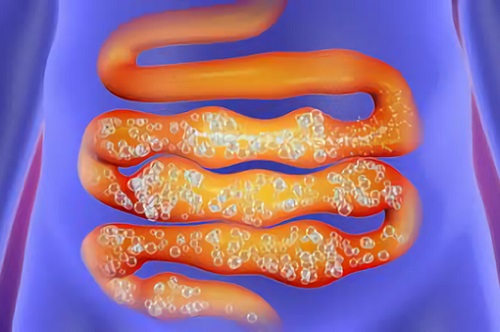

Чтобы определить ключевые факторы, необходимо понять суть самого явления. Запор представляет собой нарушение процесса формирования и продвижения каловых масс. Это может происходить из-за дисфункции мышц, ослабления позывов или необратимых изменений в структуре кишечника и близлежащих органов, что затрудняет движение продуктов жизнедеятельности по желудочно-кишечному тракту.

- Наличие синдрома раздраженного кишечника:

- постоянные нарушения перистальтики кишечника,

- периодические запоры, чередующиеся с поносом.